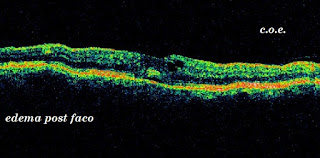

OCT retina V

Os aporto fotos de retina ( macula) , con OCT; espero que os sirvan